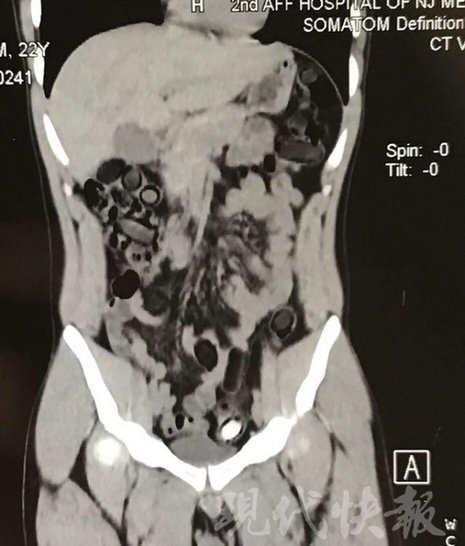

小伙體內(nèi)藏毒300余克 CT掃描圖密密麻麻

由于毒品在體內(nèi)一旦泄露有可能致命,警方第一時(shí)間將阿永帶到醫(yī)院進(jìn)行檢查。CT 掃描的結(jié)果顯示,阿永體內(nèi)布滿了密密麻麻的白色圓柱狀固體,就像一粒粒的蠶蛹。在南京市公安局鼓樓分局二板橋派出所,阿永分四次排出了毒品,毛重369.99克。經(jīng)訊問,阿永交代了自己全部的犯罪事實(shí)。目前,阿永已被刑事拘留。